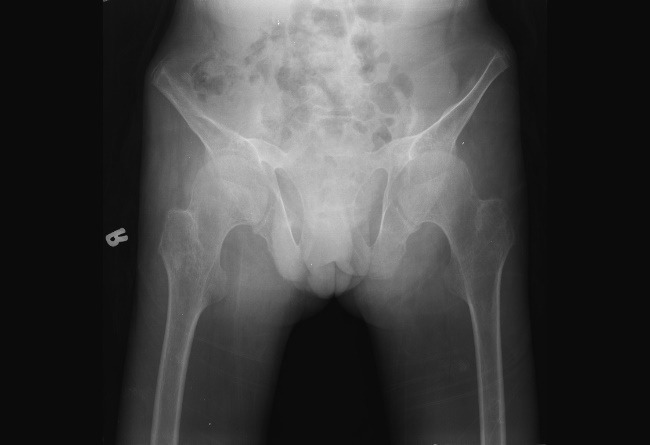

Hypopituitarism is a clinical syndrome that occurs when the anterior pituitary gland fails to secrete one or more hormones. Developmental delay is frequently seen in these patients. However, skeletal deformities and postural instability are unexceptional. We present a 17-year-old male patient with panhypopituitarism (PHP) with back and leg pain, postural malalignment, and skeletal deformities referred by the pediatric endocrinology clinic. According to the physical examination, laboratory tests, and radiographic assessments, the patient was considered as sequela spondyloarthropathy (SpA). Autoimmune and rheumatic diseases are frequently encountered in patients with hypogonadism. However, the association of PHP and ankylosing spondylitis (AS) has not yet been demonstrated. This case was presented to draw attention to the alignment of PHP and SpA and also to emphasize that skeletal deformities were not encountered in the absence of anterior hypophysis hormones.